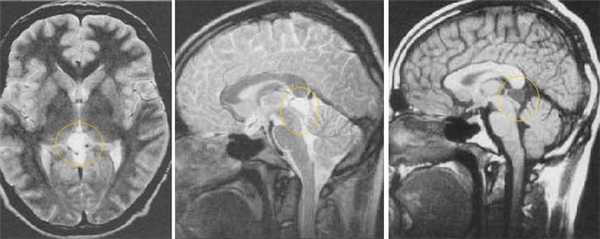

Герминома пинеальной области. На Т2 ВИ опухоль имеет слабо гиперинтенсивный сигнал по сравнению с тканью мозга, тогда как на Т1 опухоль практически изоинтенсивна с мозгом. Желудочковая система гидроцефально расширена. III желудочек деформирован. Четверохолмная пластинка оттеснена кзади.

Герминома пинеальной области. Опухоль имеет гетерогенное строение с множеством мелких и крупных кист. Вокруг опухоли определяется перифокальный отек.

Герминома подкорковых образований слева. Мультикистозного строения опухоль с признаками окклюзии отверстия Монро слева.

Злокачественная смешанная герминативноклеточная опухоль. В боковых желудочках и пинеальной области определяются множественные опухолевые узлы с выраженным перитуморальным отеком. Внутрижелудочковые образования с признаками кровоизлияний. При в/в контрастировании определяется выраженное контрастирование узлов. Дополнительно визуализируется метастазирование по эпендиме боковых и IV желудочков мозга.